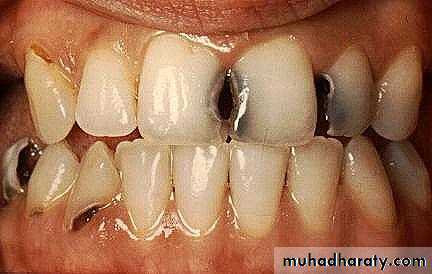

1. Evaluate the tooth to be restored Diagnostic phase

• a. Clinical examinations

• Percussion, pain

• Deep caries